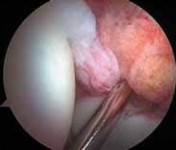

Indiscriminate débridement of the ligamentum teres should be avoided and intact fibers preserved; however, débridement of the disrupted portion can be quite beneficial ( TECH FIG 4).

Most of the contents of the acetabular fossa are best accessed from the anterior portal.

9.

However, a portion of the posterior contents often is best accessed with instrumentation introduced from the posterolateral portal.

10.

Between these two sites most pathologic processes can be accessed with combinations of straight, curved, and flexible instruments.

). B. Débridement is begun with a synovial resector introduced from the anterior portal. C. The acetabular attachment of the ligamentum teres in the posterior aspect of the fossa is addressed from the posterolateral portal. (Reprinted with permission from Byrd JWT, Jones KS. Traumatic rupture of the ligamentum teres as a source of hip pain. Arthroscopy 2004;20:385–391.) PEARLS AND PITFALLS Patient selection Patient positioning Portal placement Avoid iatrogenic damage Avoid excessive labral resection Avoid advanced disease states